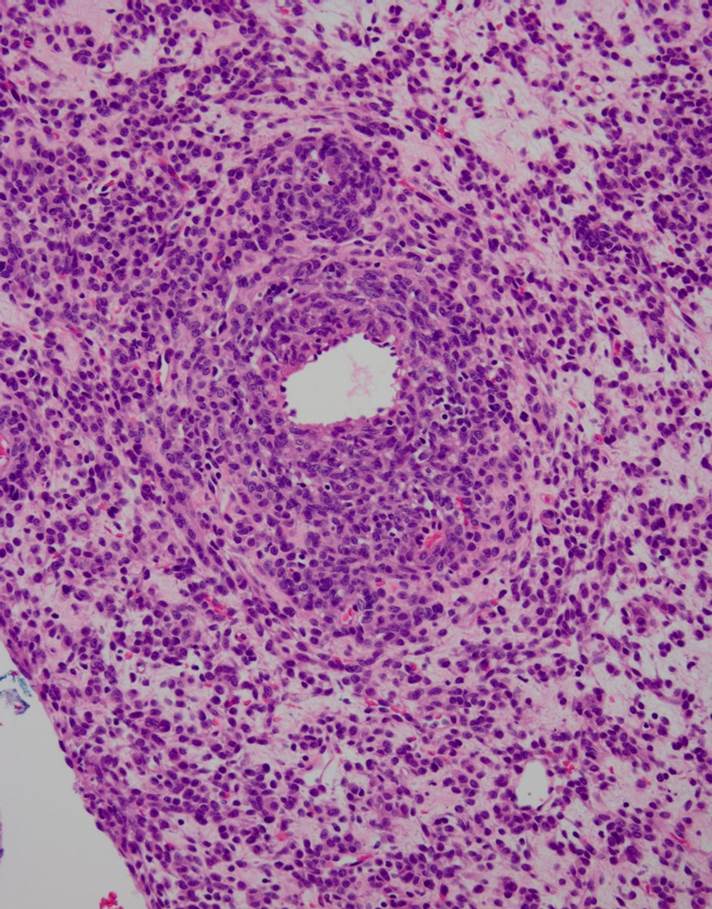

40 year old female with pelvic mass and friable cervix, biopsy was performed at OSH....